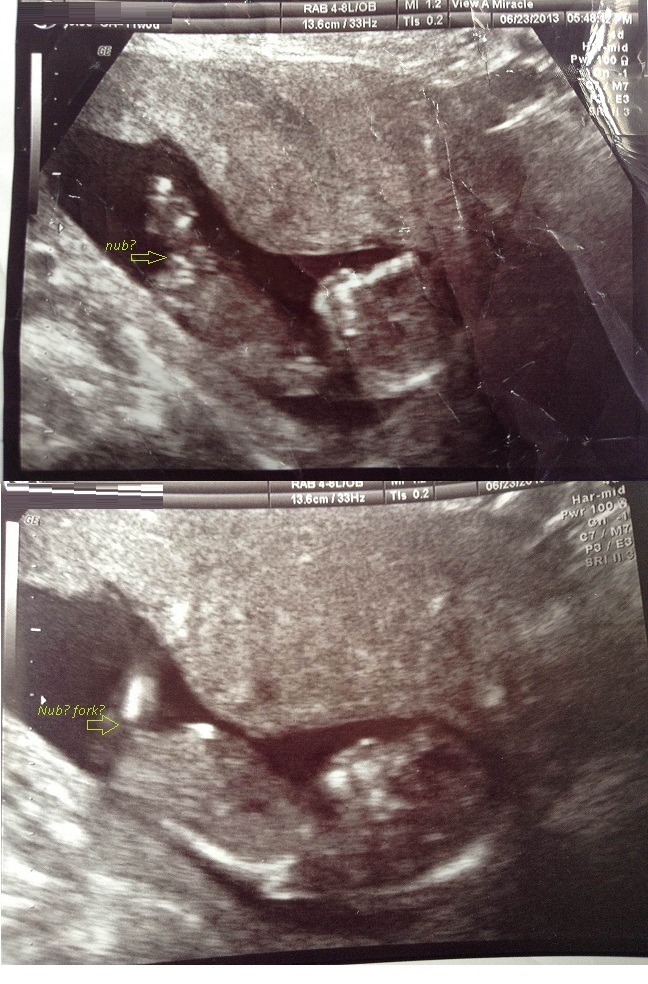

I am no expert, but that looks girly to me. What are you hopving for?

I would also guess girl

Looks girly. :)

The nub is straight so I would guess girl too! :)

I'm not positive either image is showing the nub. But if it is then it looks girly.